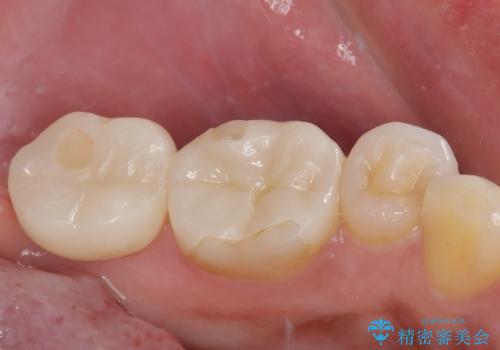

抜歯即時インプラントで治療期間を大幅短縮!抜歯からセラミックまでを3か月で完了

- 3ヶ月

- 2-5回

- 44万円(税込)費用は治療当時の料金となります